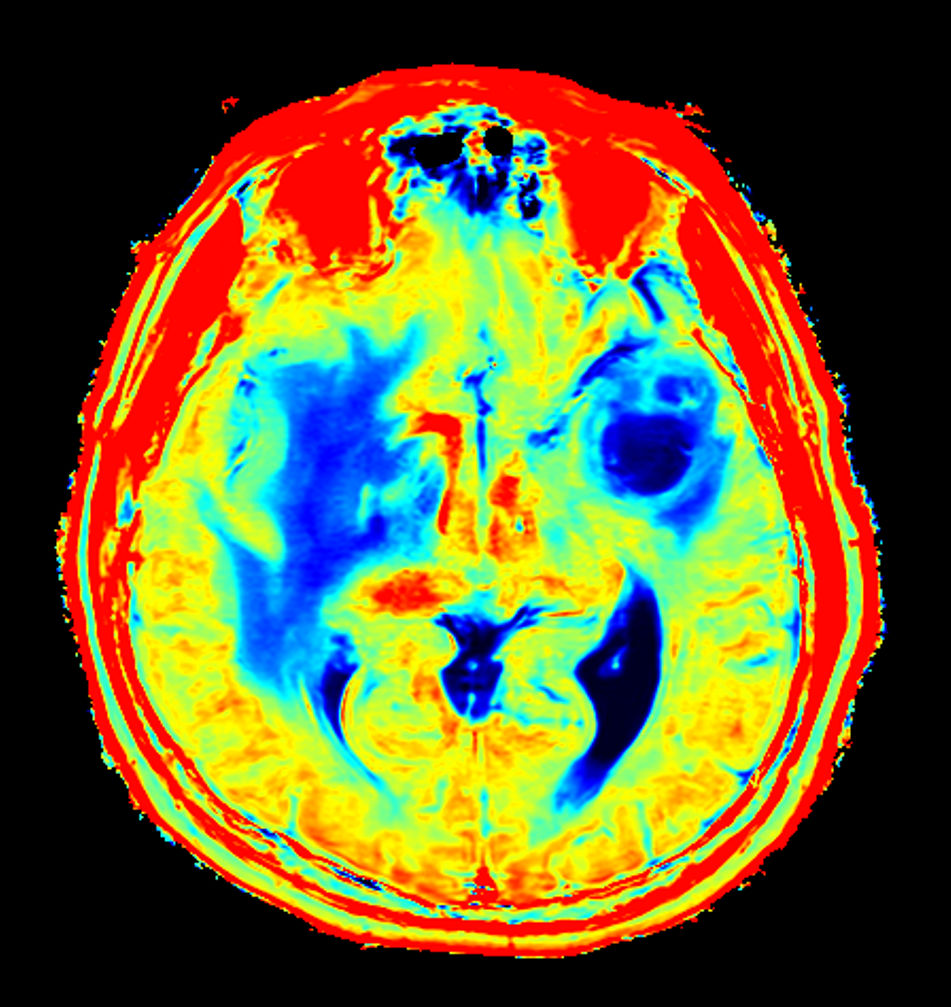

Axial T2* Perfusion (TTP)